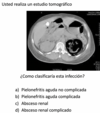

3

Q

pielo aguda complicada

en una pielonefritis aguda complicada